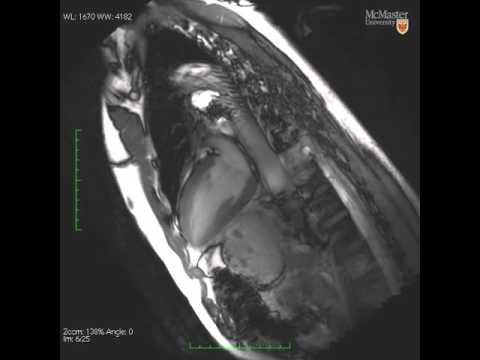

MRI video of the human heart